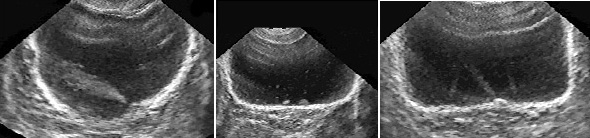

Установить положение точечных устий помогают выбросы из мочеточников (рис. 3). Это явление можно наблюдать в 30−40% исследований мочевого пузыря. при форсировании мочевыделения диуретиками выявляемость эффекта достигает 70−80% [4,17]. В цветном допплеровском режиме выбросы можно обнаружить практически во всех случаях. Визуализация этого сонографического феномена связана с эффектом псевдоконтрастирования турбулентной струи мочи, выбрасываемой в мочевой пузырь при сокращении нижнего цистоида мочеточника. На контрастность визуализации выбросов влияет также разность плотностей пузырной и мочеточниковой мочи [3,10].

Рис. 3. Сонограммы мочевого пузыря в норме и при аномалиях развития почек и мочеточников. Выбросы из мочеточников помогают установить положение и число устий, подтвердить тем самым наличие одной, двух или трех функционирующих почек (Поперечное сканирование, секторный датчик 5 МГц, “Siemens SL-1”).